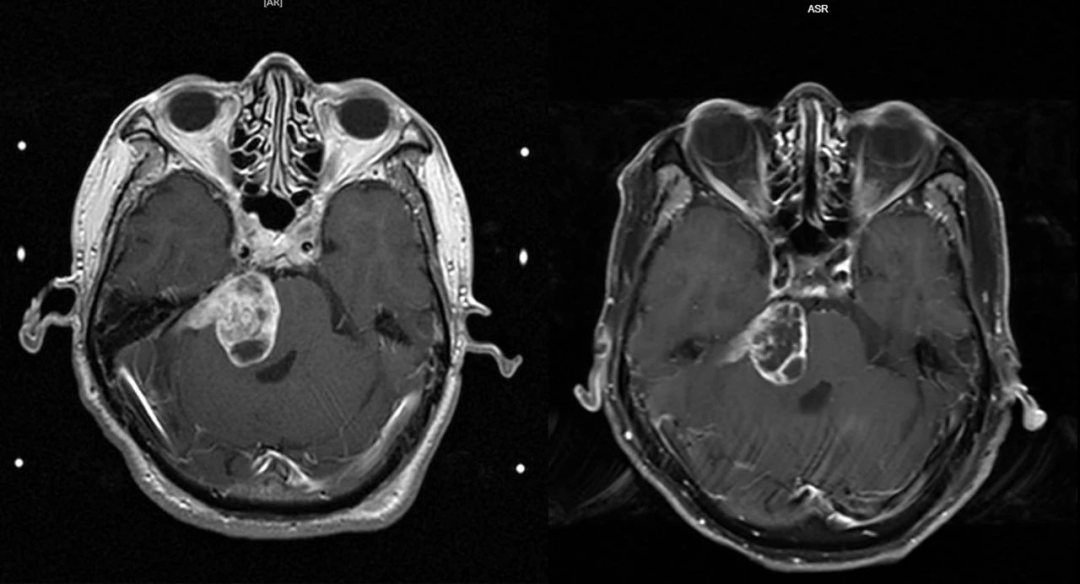

坎坷的抗癌历程让李先生成功度过5年生存期,但是在第十个年头复查时,颅脑MR平扫+增强诊断为:听神经瘤术后复发。

治疗结束后,李先生病情平稳, 精神状态好,肿瘤较入院前明显缩小。

(入院前后MRI)